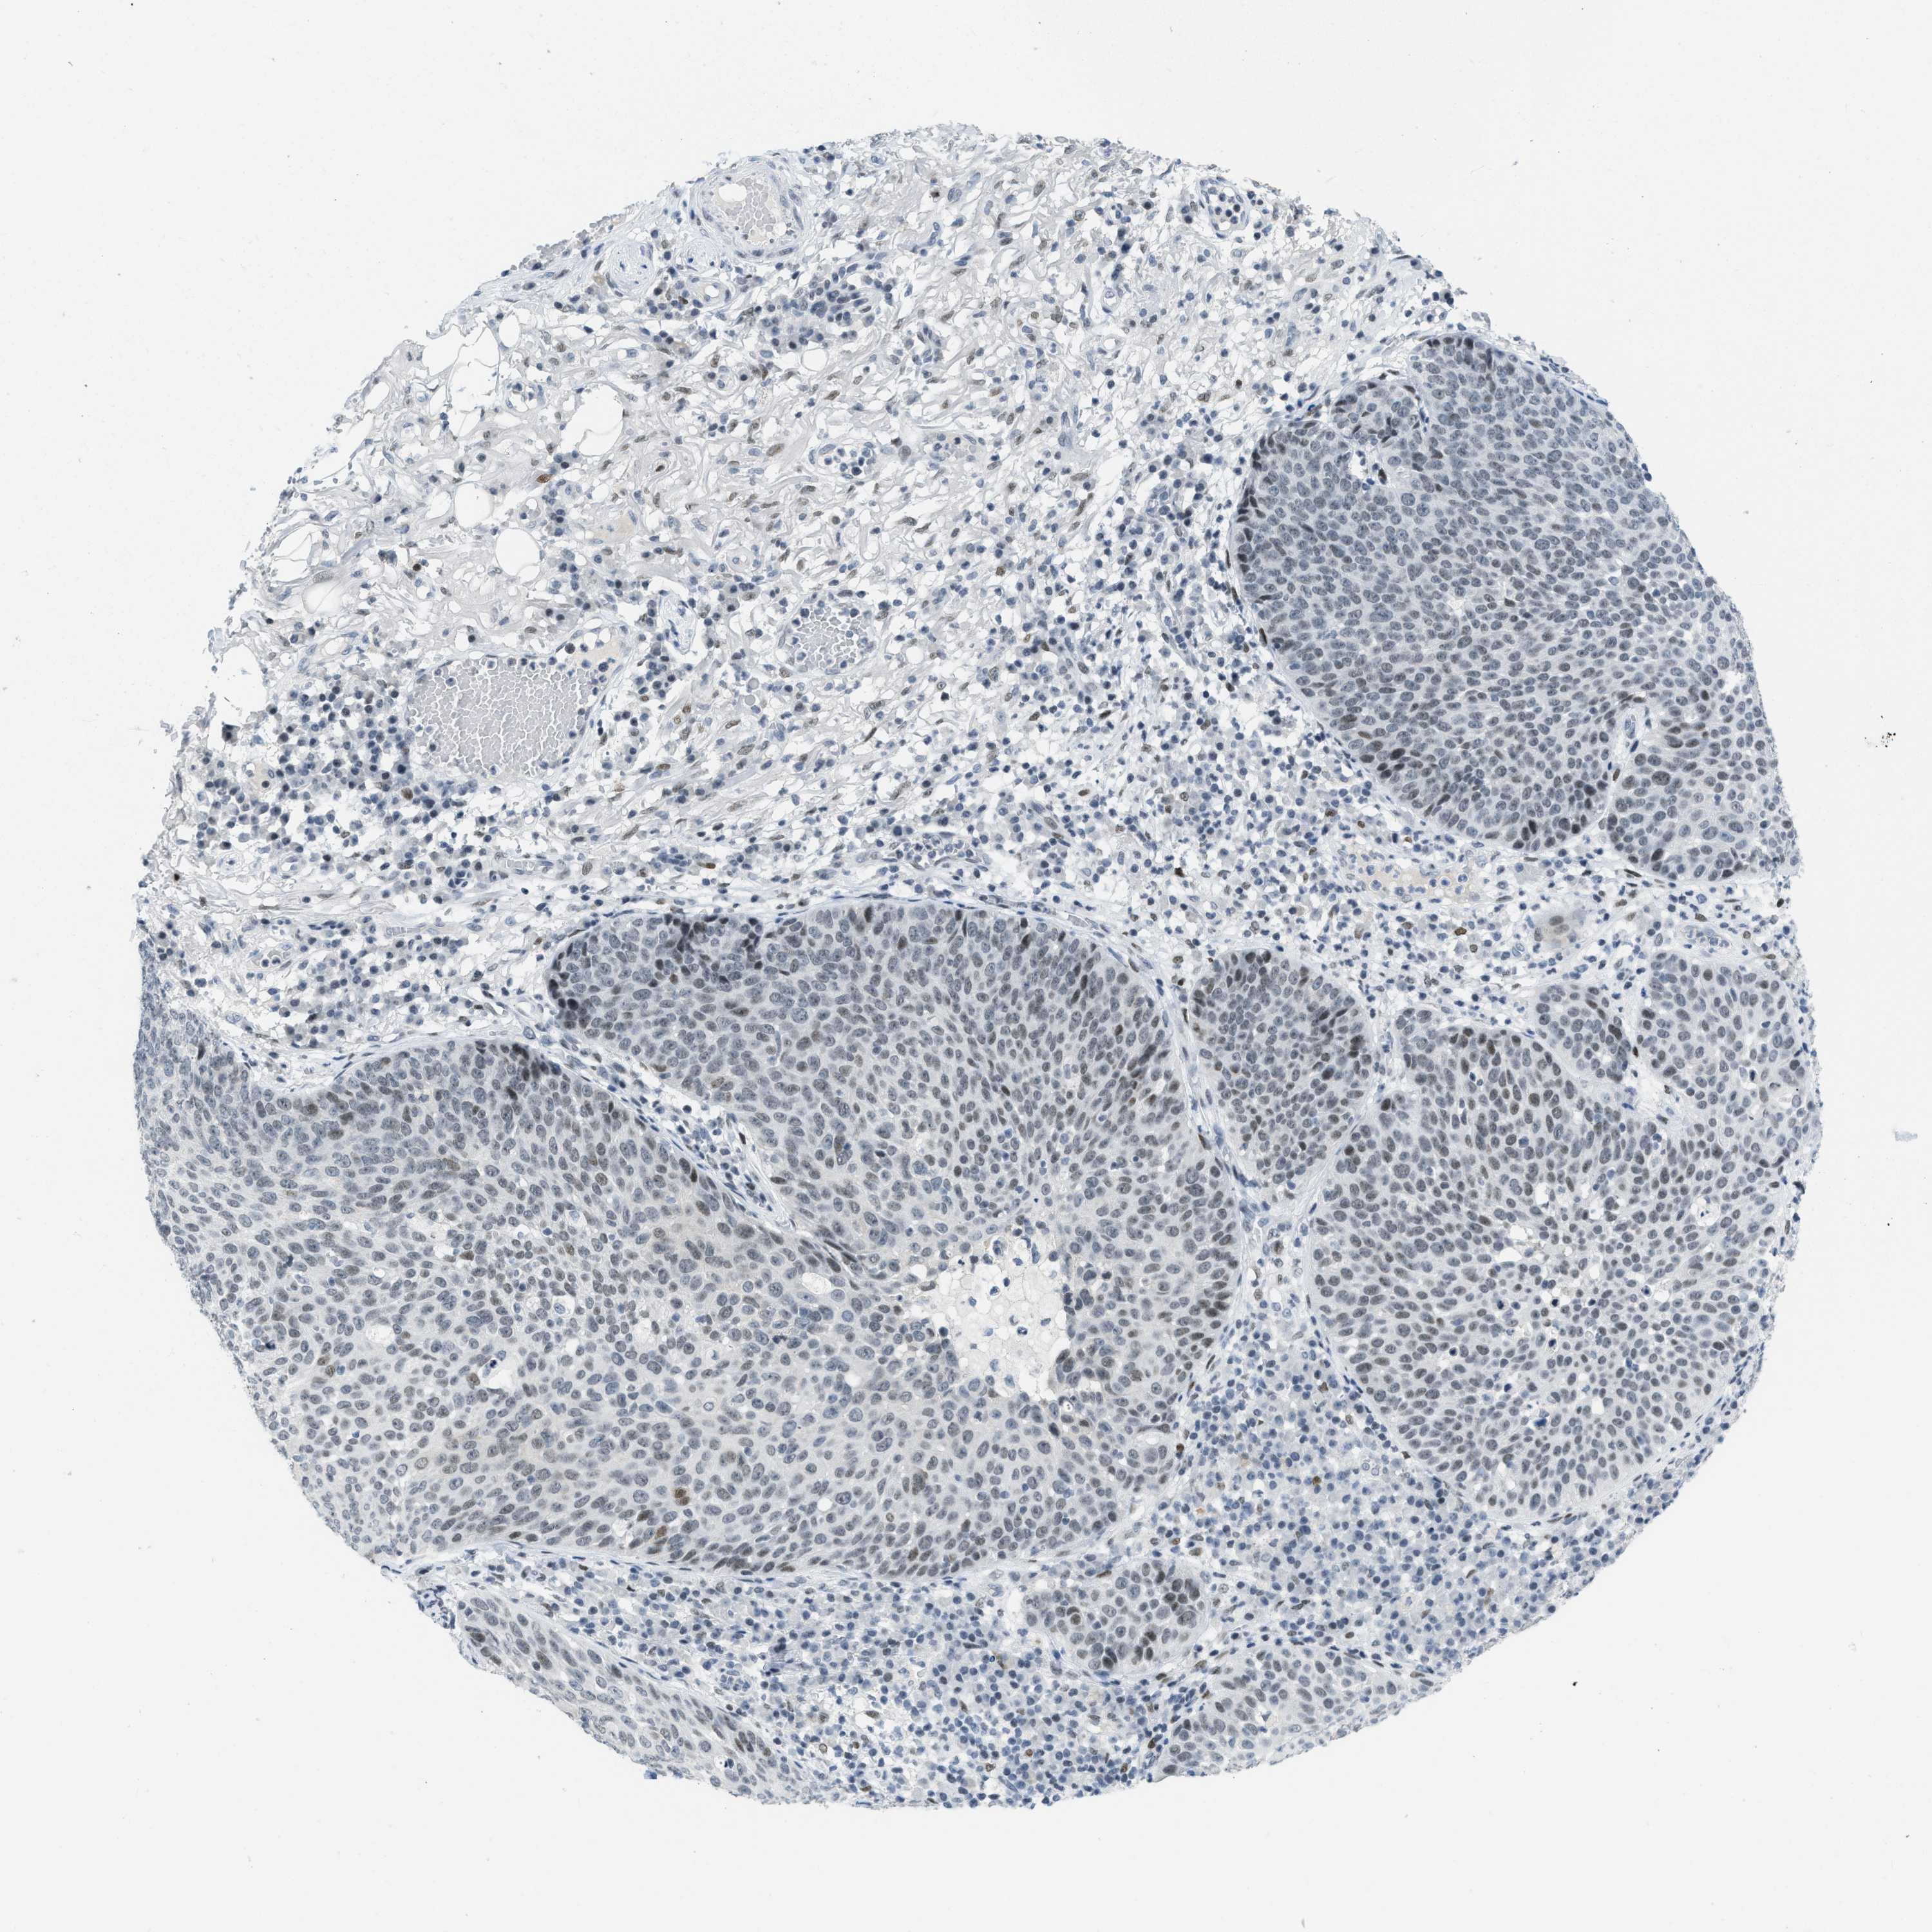

SKIN CANCER - Protein expressioni

A mouse-over function shows sample information and annotation data. Click on an image to view it in a full screen mode. Samples can be filtered based on level of antibody staining by selecting one or several of the following categories: high, medium, low and not detected. The assay and annotation is described here.

Each image is clickable and will lead to virtual microscopy that enables deeper exploration of all samples and also displays staining intensity scores, fraction scores and subcellular localization as well as patient and tissue information for each sample.

Antibody HPA003505

Squamous cell carcinoma, NOS

Basal cell carcinoma

Squamous cell carcinoma in situ, NOS

Squamous cell carcinoma, metastatic, NOS